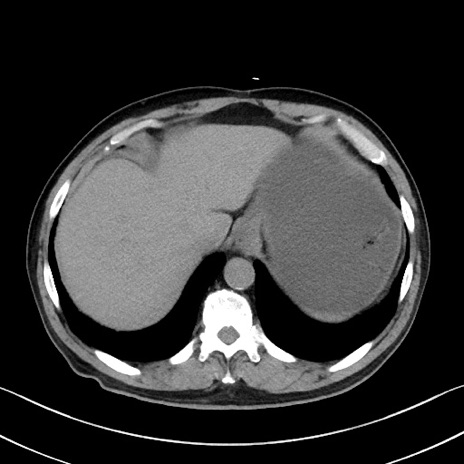

症例35(横断像)

【症例】70歳代 男性

【主訴】腹部膨満、嘔吐

【現病歴】昨日より腹部膨満感出現。本日増悪し、仙痛出現。嘔吐あり、受診。

【既往歴】糖尿病、胆摘後

【身体所見】BP 149/80mmHg、HR 74/min、BT 35.9℃、腹部:膨満、軟、圧痛なし。腸雑音減弱あり。上腹部正中切開瘢痕あり。

【データ】WBC 13500、CRP 1.72